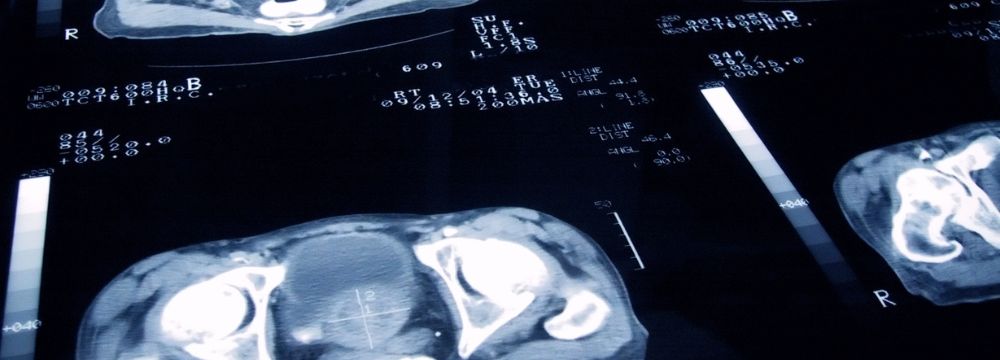

The prostate is a walnut-shaped organ located in front of a man’s urinary bladder and surrounding his urethra. After age 40, the prostate typically enlarges–a condition known as benign prostatic hypertrophy (BPH). BPH causes symptoms such as urinary retention, bladder infection, poor urine flow, and more.

Prostate Cancer Diagnosis and Treatment

If you have concerns about prostate cancer, you should see a urologist for testing. If necessary, you’ll be referred to a urological oncologist. This kind of physician understands the various types of and treatments for cancers of the genitourinary tract.